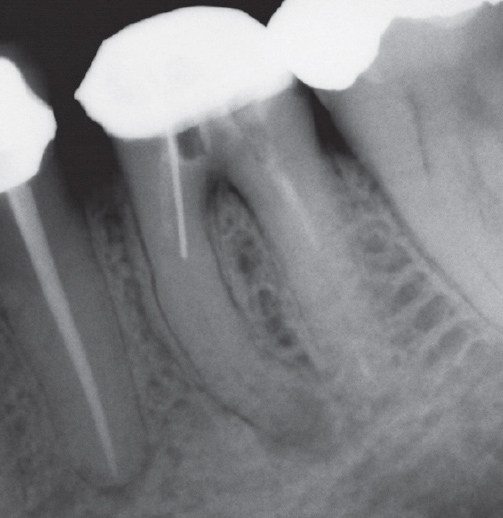

After

After Root Canal treatment